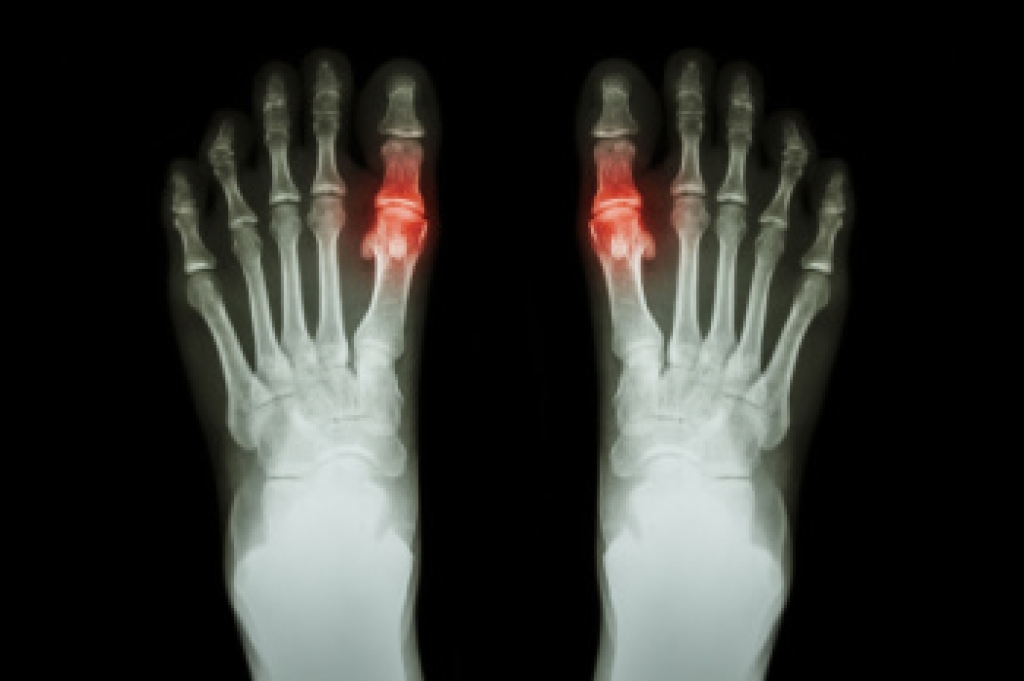

Gout